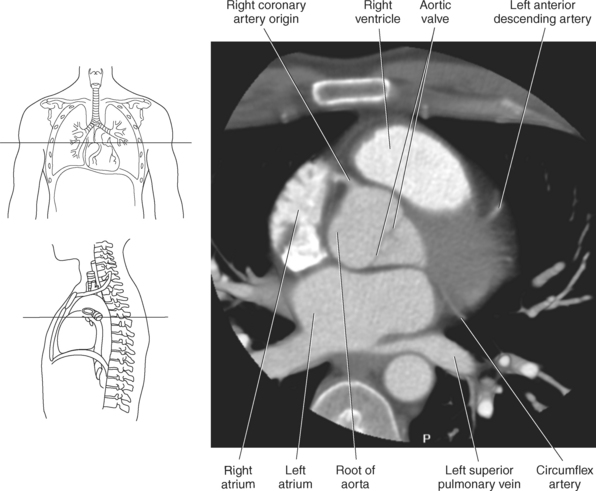

The two main coronary arteries are the first vessels to branch off the ascending aorta (Figures 6.91 and 6.92). The right coronary artery arises from the base or root of the aorta (right aortic sinus) and passes anteriorly between the pulmonary trunk and right atrium to descend in the coronary (atrioventricular) groove. As it reaches the diaphragmatic surface, it gives off a right marginal branch that runs toward the apex of the heart. The right coronary artery then turns to the left and enters the posterior interventricular groove, where it gives off the posterior interventricular branch (posterior descending artery). The posterior interventricular branch continues to descend along the interventricular groove toward the apex, where it anastomoses with the left anterior descending artery of the left coronary artery. The right coronary artery and its branches supply the right atrium, right ventricle, interventricular septum, and the sinoatrial (SA) and atrioventricular (AV) nodes. It also supplies a portion of the left atrium and ventricle (Figures 6.92 through 6.96). The left coronary artery arises from the left aortic sinus and passes to the left between the pulmonary trunk and left atrium to reach the coronary groove (Figures 6.91 and 6.92). Soon after reaching the coronary groove, the left coronary artery divides into the circumflex and left anterior descending (interventricular) arteries. The circumflex artery winds around the left border of the heart to the posterior surface, where it gives off the left marginal artery. The left anterior descending artery (LAD) descends in the anterior interventricular groove toward the apex of the heart, where it reaches the diaphragmatic surface to anastomose with the posterior descending artery. The left coronary artery and its branches supply the interventricular septum, including the AV bundles, and most of the left ventricle and atrium (Figures 6.97 through 6.99).